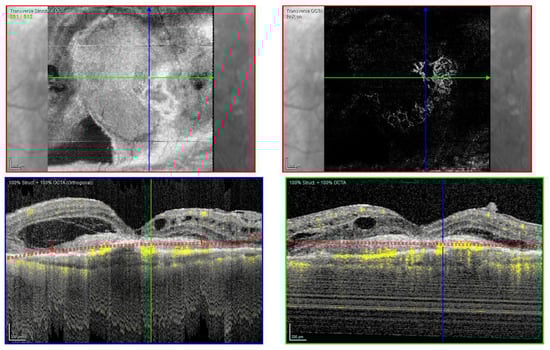

Fundus examination showed a macular yellowish elevated lesion in both eyes (Figure 6A,B). FAF revealed a hypoautofluorescent macular lesion (Figure 6C,D).

Figure 6.

Case 5. Multimodal imaging features of bacillary layer detachment (BALAD) in neovascular age-related macular degeneration patients in both eyes. (A,B) Optos Ultra-widefield colour shows a macular yellowish slightly elevated macular lesion. (C,D): Optos Ultra-widefield autofluorescence imaging shows a hypoautofluorescent macular lesion. (E) Heidelberg Spectralis optical coherence tomography shows a type 1 MNV with subretinal and intraretinal fluid and BALAD in the right eye. (F) Heidelberg Spectralis optical coherence tomography shows a type 1 MNV with subretinal fluid and BALAD in the left eye.

The OCT showed a type 1 MNV with a fibrovascular PED, subretinal fluid, and BALAD in both eyes (Figure 6E,F).

The OCTA scan confirmed the presence of MNV (Figure 7A,B).

Figure 7.

Case 5. Heidelberg Spectralis optical coherence tomography angiography shows a subretinal neovascular membrane in right (A) and left eyes (B).

Over the years, these features have shown improvement phases alternating to worsening ones.

The patient is still on treatment with anti-VEGF intravitreal injections (T&E regimen) for both eyes.

The BCVA has been stable throughout the treatment period. When last examined, it was 0.63 logMAR in the right eye and 0.32 logMAR in the left eye.